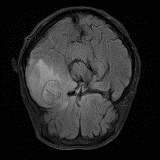

We obtain a subject-wise mean Dice score of 63.67% for the brain tumor segmentation. Utilizing a simple post-processing scheme of erosion and dilation with filter, we improve our mean Dice score to 68.01%. Figure 4 shows samples generated by our ASC-Net and Table 2 shows our before and after post-processing results. We attempted to apply f-AnoGANs [34] by following their online instructions and failed to generate good reconstructions as shown in Figure 5. The failure of AnoGANs in the reconstruction brings to light the issue with the regeneration based methods and the complexity and stability of GAN-based image reconstruction.

The Flair experiment results are obtained using a training of two cycles in the first stage and four cycles in the second stage to reach the peak separation, and the threshold value is taken at the intensity of 170. For T2 we use two cycles in the first stage and two cycles in the second stage, and the threshold is taken at 220. Both thresholds are taken based on the rightmost peaks of the histograms of reconstructed images. We obtain a subject-wise mean dice score of 79.89% on the Flair scans and 88.57% on the T2 scans. Despite the lower score compared to T2, the Flair modality provides the potential of identifying additional anomalies, which may not be limited to HGG or LGG, as shown in the third column of Fig. 6. However, since the focus of this experiment is to segment HGG and LGG only, using the T2 modality outperforms the Flair in term of the Dice scores as reported in Table 2, and the predicted masks as shown in Fig. 6. Aside from that, on the Flair scans our method suffers both under- and over-segmentation as shown in Fig. 7 and struggles to segment tumors using one uniform threshold as shown in Fig. 8. Typically, we use the rightmost peak as the threshold for brighter tumors; however, the peaks separating tumors in these cases of Fig. 8 occur as the leftmost peak. Such flip further lowers the segmentation score, even though the algorithm is able to separate the anomaly as one of the two cuts.

Although our method has consistently better performance of segmenting brain tumors on T2, as shown from Fig. 6 to Fig. 8. In the case of T2, the primary disadvantages occur due to the inclusion of other regions, such as Cerebrospinal Fluid (CSF), eyeballs, etc., which appear dark in the Flair modality. In order to alleviate these false positives on T2 scans, we multiply the predicted masks with the Flair input images. Then we re-calibrate the output by taking a threshold at the intensity of 50 (roughly 0.2 in the range [0,1]) to generate our final mask. This post-processing is our new choice for the private dataset. We did not use the erosion/dilation operation because it is more efficient for cases with discontinuous segmentation results, which is the one our public datasets suffer with, as shown in Fig. 4, but not our private dataset. This new post-processing improves the performance to a patient-wise mean dice score of 91.58% on T2 scans with two-fold cross validation.